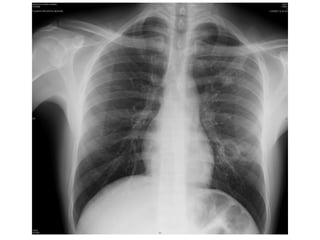

Case I

• A 35 year old housemaid,

• C/O chest pain with deep breathing with

blood stained sputum for last 2 weeks

• DM II +ve

• CXR

Case I • A35 year old housemaid, • C/O chest pain with deep breathing with blood stained sputum for last 2 weeks • DM II +ve • CXR